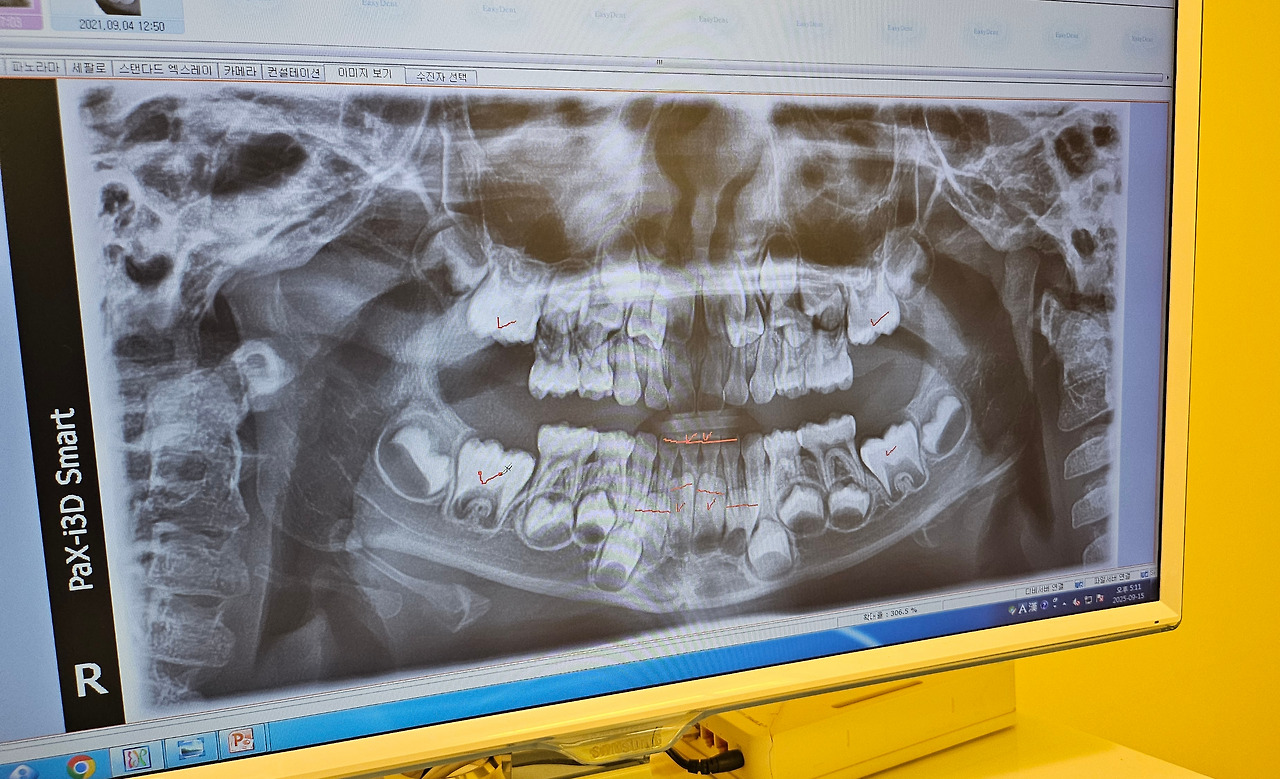

이제 곧 이빨이 빠지고, 새 이빨이 난다고 한다. 그런데 조그마한 문제가 있다고 한다. 새 이빨이 올라오고 있는데, 아랫니가 나올 공간이 부족하다고 한다. 사진을 보여주셨는데, 확실히 좁다. 교정이 필요하다고 하신다. 세상에.... 이런 데서 유전의 힘이. 아이의 이가, 나랑 똑 닮았다. 아니, 아빠 할머니와 똑 닮았다. 나와 어머니는 아랫니 치열이 고르지 못하다. 이빨 하나가 뒤로 빠져있다. 아마 아이 이빨의 예정된 미래가 곧 아빠 이빨일 듯하다.

20250915_171130.jpg 아랫니 4개가 나올 공간이 없다고 설명 주셨다. 사진은 찍어도 된다고 하셔서 기념상 찰칵.